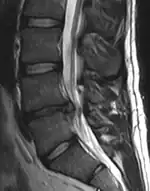

- Magnetic resonance imaging is the gold standard study for confirming a suspected LDH. With a diagnostic accuracy of 97%, it is the most sensitive study to visualize a herniated disc due to its significant ability in soft tissue visualization. MRI also has higher inter-observer reliability than other imaging modalities. It suggests disc herniation when it shows an increased T2-weighted signal at the posterior 10% of the disc. Degenerative disc diseases have shown a correlation with Modic type 1 changes. When evaluating for postoperative lumbar radiculopathies, the recommendation is that the MRI is performed with contrast unless otherwise contraindicated. MRI is more effective than CT in distinguishing inflammatory, malignant, or inflammatory etiologies of LDH. It is indicated relatively early in the course of evaluation (<8 weeks) when the patient presents with relative indications like significant pain, neurological motor deficits, and cauda equina syndrome. Diffusion tensor imaging is a type of MRI sequence used for detecting microstructural changes in the nerve root. It may be beneficial in understanding the changes that occur after herniated lumbar disc compresses a nerve root, and might help in differentiating the patients that need surgical intervention. In patients with a high suspicion of radiculopathy due to lumbar disc herniation, yet the MRI is equivocal or negative, nerve conduction studies are indicated.[44] T2-weighted images allow for clear visualization of protruded disc material in the spinal canal.

Example of a herniated disc at L5–S1 in the lumbar spine